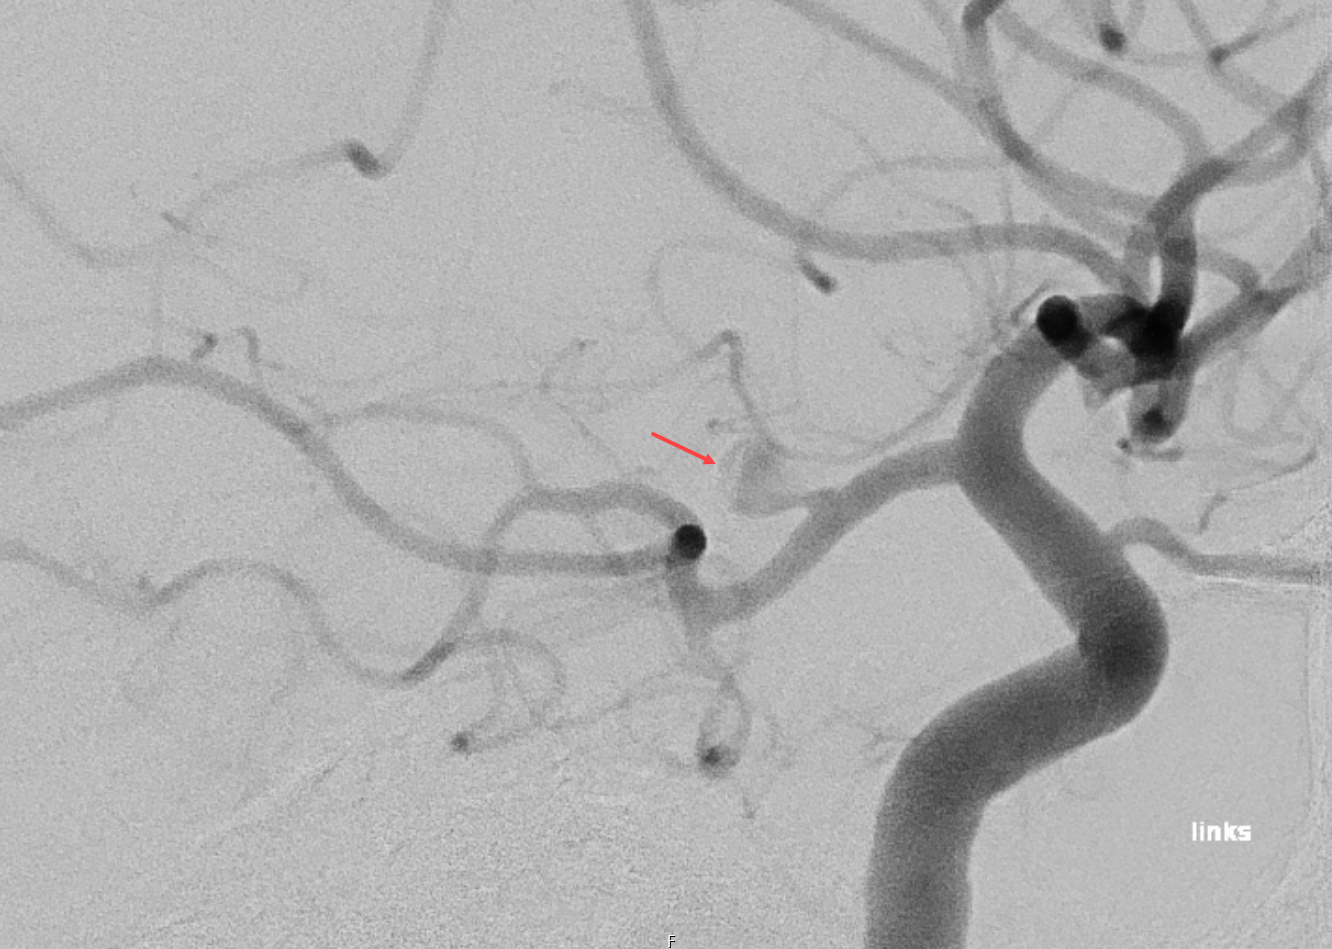

Der Goldstandard zur Visualisierung eines PCOM Aneurysma ist die digitale Subtraktionsangiographie. Rupturierte PCOM Aneurysmen können typischerweise neben einer Subarachnoidalblutung auch eine Subduralblutung verursachen5.